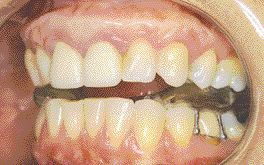

FIGURE 13--Repositioning splint.

Most general dentists do not have any desire to treat patients with TM dysfunction. They do not feel that they had proper training in dental school and many are not interested in attending postgraduate courses. I developed an interest in the TM joint when I first attended courses sponsored by the University of Toronto 21 … Read more